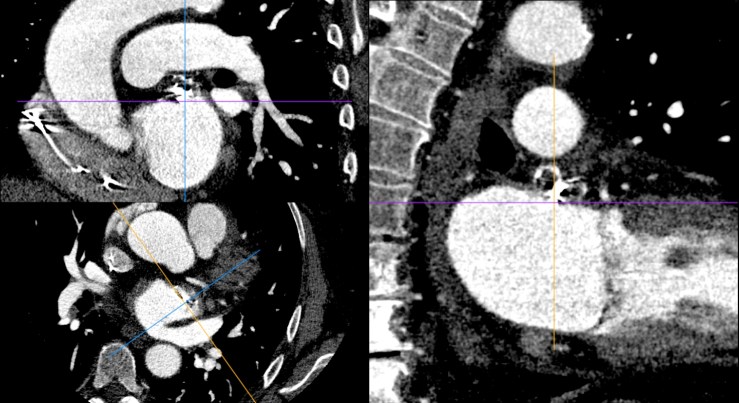

Και στις MPR τομές, να μη φαίνεται σκιαγράφηση του σώματος του ωτίου — ακόμα και ένα μικρό peri-device leak (PDL) θα τo «ασπρίσει» –, ούτε βέβαια θρόμβος (device-related thrombosis, DRT).

Για σύγκριση, οι εικόνες CTA\ECG πριν την τοποθέτηση της συσκευής: